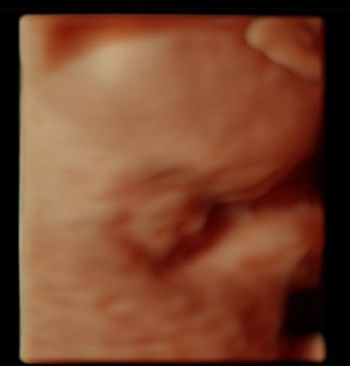

Challenge your anatomy knowledge; what body part is this 3-D image showing?